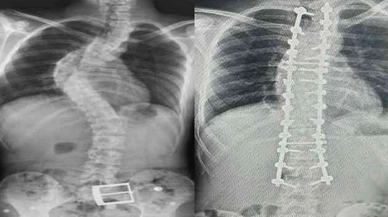

skolyoz haberleri

skolyoz haberleri ve güncel skolyoz gelişmeleri, skolyoz ile ilgili tüm video, skolyoz fotoğrafları ve skolyoz haberleri Sivas Haberleri - Sivas Son Dakika Haberleri - Bizim Sivas Haber sitemizde